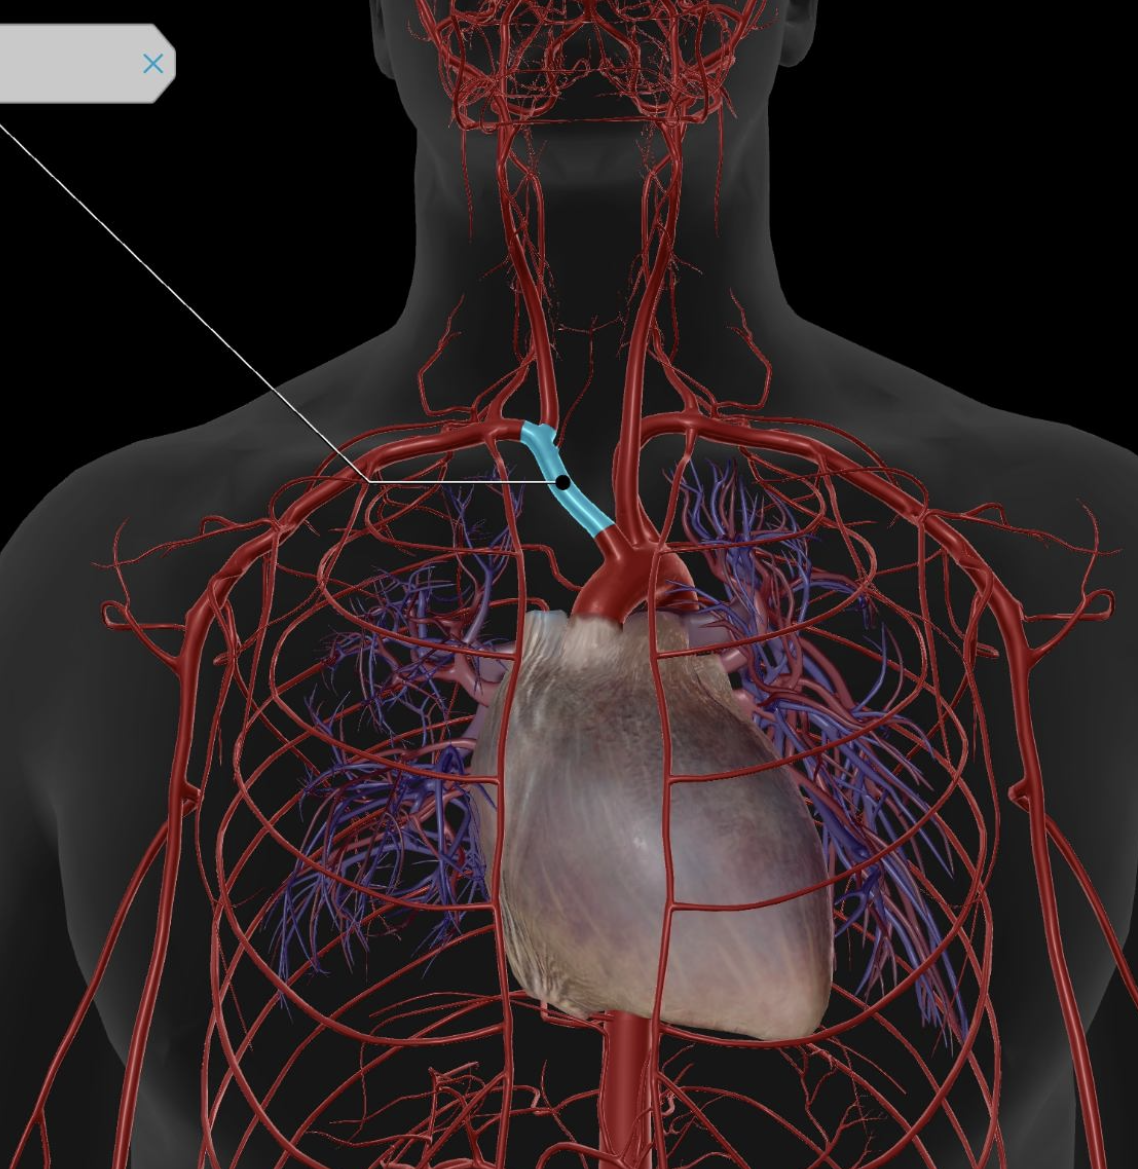

Subclavian Artery

Subclavian Vein

Brachiocephalic Trunk

Brachiocephalic Vein